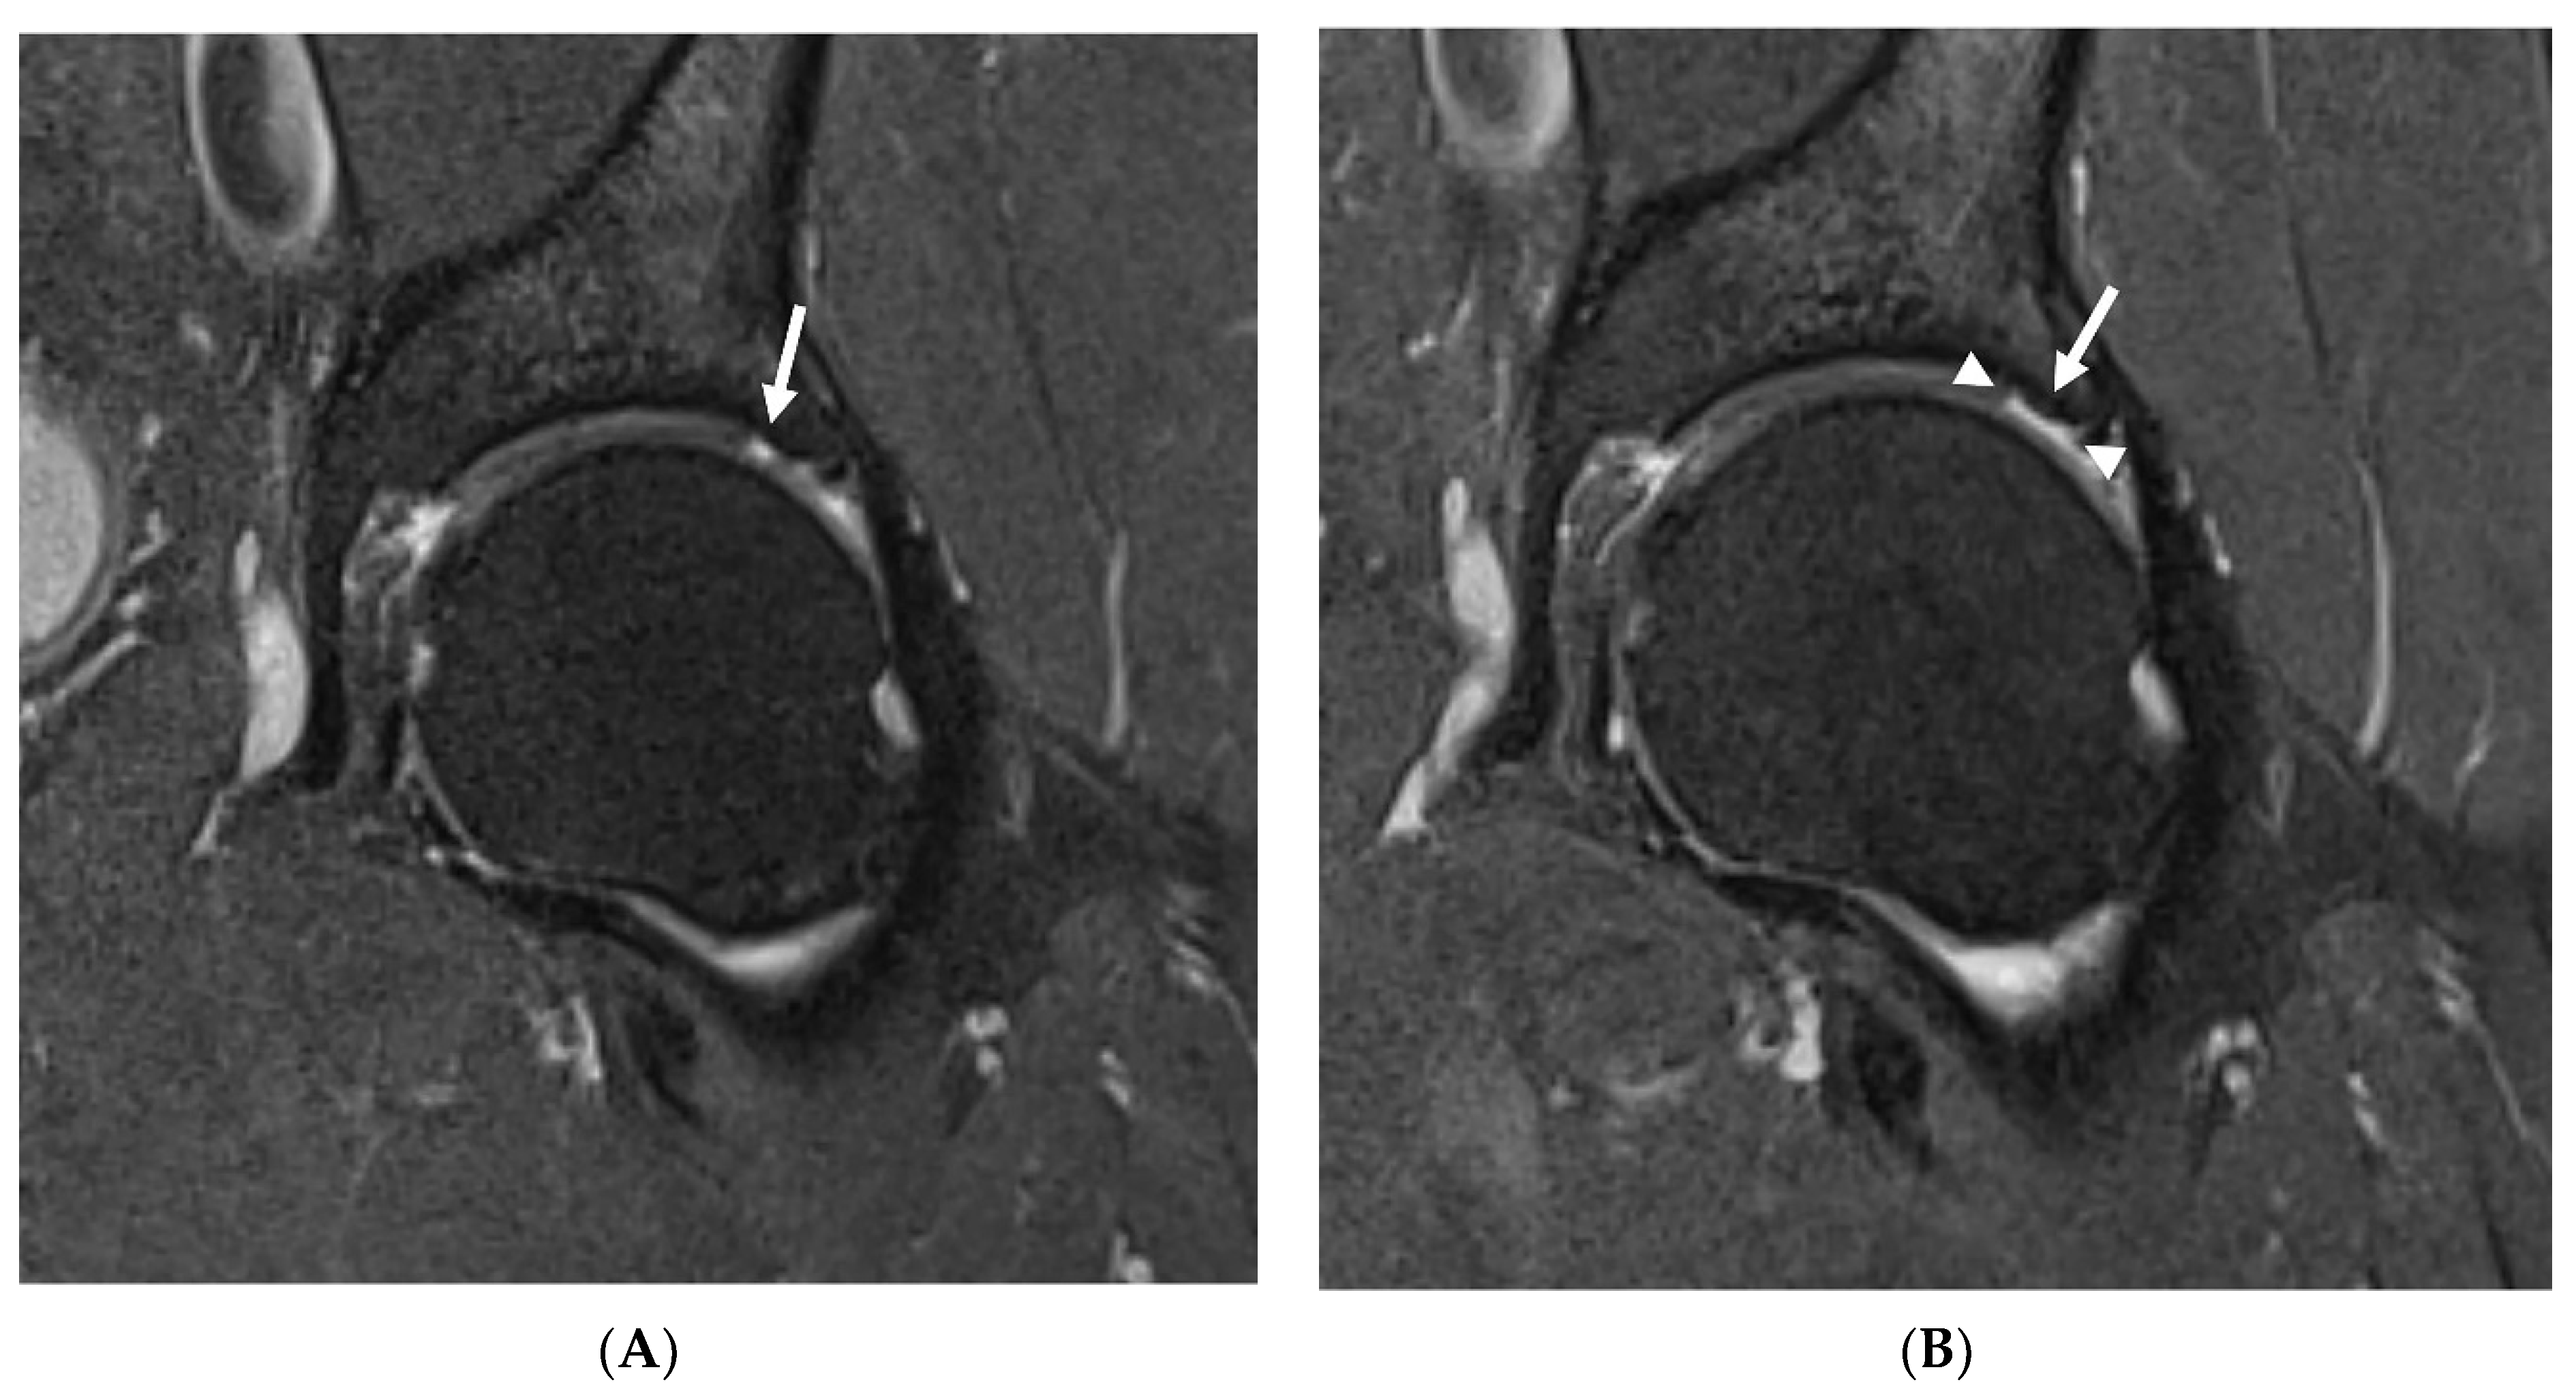

In the study group, no statistically significant changes in any of SHORMI subscales were observed during the 12-month follow-up. However, on an individual basis, two patients showed a progression of cartilage defects reflected by a change in the SHORMI score from 1 to 2, and one patient showed a progression of subchondral cysts similarly reflected by an increase in the SHORMI score. In three patients, enlargement of cartilage defect area was observed; however, since those were already full-thickness defects, it did not affect SHORMI score (Figure 1); in one of those patients the area of bone marrow edema increased as well. In one patient, the paralabral cyst increased substantially. All of those patients (n = 7) were labeled “progressors”, in contrast to the remaining patients (n = 17) that showed no change in MRI (“non-progressors”) (Table 5). This division was subsequently used in further analysis.

Figure 1. Progression of chondral defects missed by SHOMRI. Baseline MRI (A) showing a full thickness cartilage defect (arrow) corresponding to SHOMRI grade 2 in a superolateral acetabular region in a 60-year-old patient. In a follow-up study (B), the defect covers a larger area (arrowheads show the margins of the defect), which still corresponds to SHOMRI grade 2.